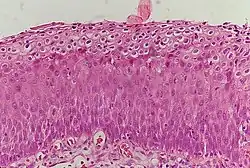

CIN is classified in grades:[17]

| Histology grade | Corresponding cytology | Description | Image |

|---|---|---|---|

| CIN 1 (Grade I) | Low-grade squamous intraepithelial lesion (LSIL) |

|

| CIN 2/3 | High-grade squamous intraepithelial lesion (HSIL) |

| CIN 2 (Grade II) |

![]() | |

| CIN 3 (Grade III) |

![]() |